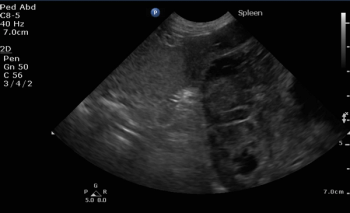

A renowned veterinary oncologist outlines the current knowledge about this cancer of the blood vessel walls, from presentation to prognosis.